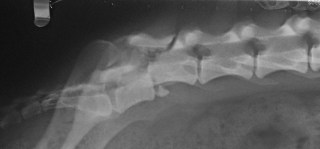

Στα ακτινογραφήματα, τα σπλάγχνα του θώρακος και της κοιλίας ελέγχθηκαν κατά φύση. Κατά τον έλεγχο της σπονδυλικής στήλης διαπιστώθηκαν εξάρθρημα μεταξύ του έκτου και του εβδόμου οσφυϊκού σπονδύλου και κατάγματα του σώματος, της ακανθώδους απόφυσης και του ραχιαίου πετάλου του έκτου οσφυϊκού σπονδύλου (Εικ. 1). Κατά τον έλεγχο της πυέλου διαπιστώθηκε προκοτύλιο-υπερκοτύλιο εξάρθρημα του δεξιού ισχίου.

Εικ.1: Ακτινογραφία της οσφυϊκής μοίρας της σπονδυλικής στήλης